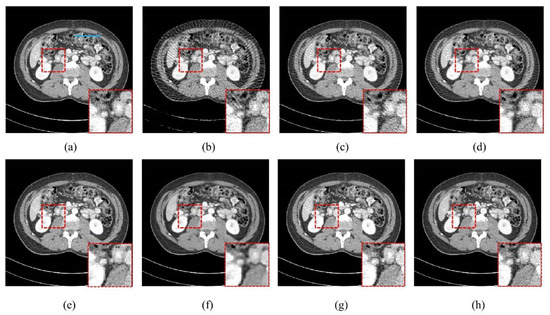

4.1. Visualization-Based Evaluation